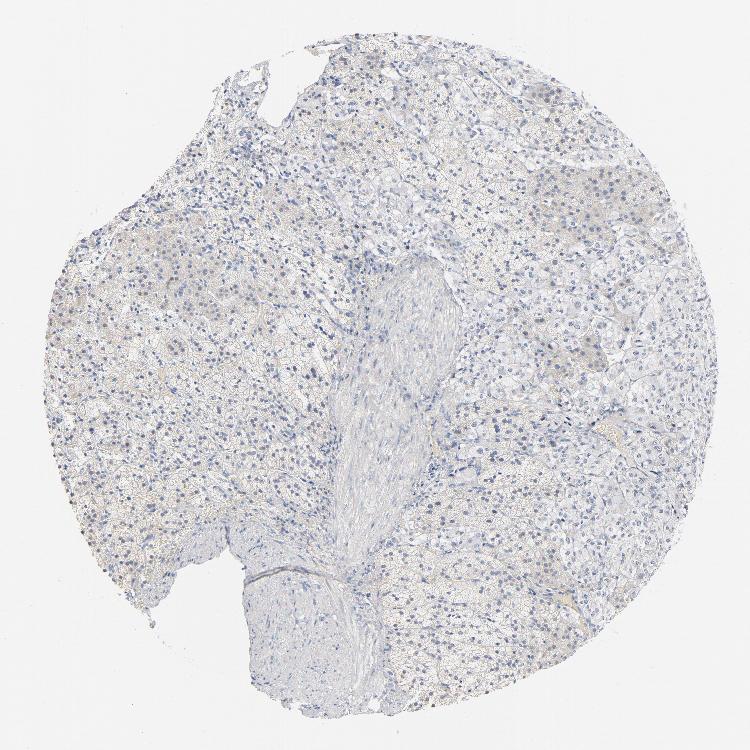

ADRENAL GLAND - Antibody stainingi

Antibody staining in the annotated cell types in the current human tissue is reported as not detected, low, medium, or high, based on conventional immunohistochemistry profiling in selected tissues. This score is based on the combination of the staining intensity and fraction of stained cells.

Each image is clickable and will lead to virtual microscopy that enables deeper exploration of all samples and also displays staining intensity scores, fraction scores and subcellular localization as well as patient and tissue information for each sample.

Antibody HPA003418Antibody CAB000376

Glandular cells Not detectedNot detected